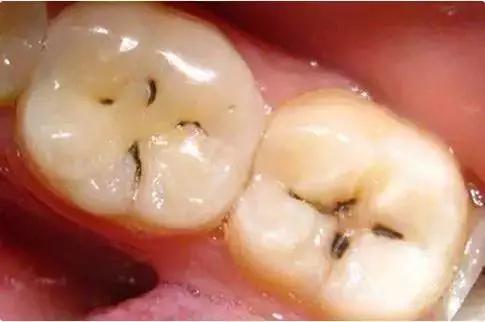

蛀牙初期 症状:牙齿上有小黑线和小黑点,牙斑 做法:初期是预防的zui

龋齿初期图片

龋齿初期图片,龋齿的发展过程图片

龋齿的发展过程图片

龋齿的三个阶段图